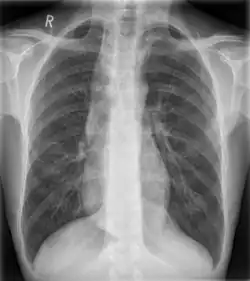

| Widened mediastinum | |

| Other names | Mediastinal widening |

![]() | |

| Widened mediastinum in a patient with achalasia | |

Widened mediastinum/mediastinal widening is where the mediastinum has a width greater than 6 cm on an upright PA chest X-ray or 8 cm on supine AP chest film.[11]

A widened mediastinum can be indicative of several pathologies:[12][13]

- aortic aneurysm[14]

- aortic dissection[15]

- aortic unfolding

- aortic rupture

- hilar lymphadenopathy

- anthrax inhalation - a widened mediastinum was found in 7 of the first 10 victims infected by anthrax (Bacillus anthracis) in 2001.[16]

- esophageal rupture - presents usually with pneumomediastinum and pleural effusion. It is diagnosed with water-soluble swallowed contrast.

- mediastinal mass

- mediastinitis

- cardiac tamponade[17]

- pericardial effusion

- thoracic vertebrae fractures in trauma patients.